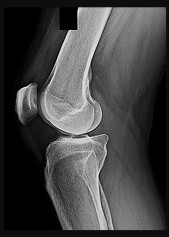

Question 5:

When performing an anterior cruciate ligament (ACL) reconstruction using a bone-patellar tendon-bone autograft, placement of the femoral tunnel too anteriorly (shallow) will most likely result in:

Correct Answer: Increased laxity in extension and tightness in flexion

Explanation:

If the femoral tunnel is placed too anteriorly, the graft will be tight in flexion and loose in extension. Conversely, if it is placed too posteriorly (deep), it will be tight in extension and loose in flexion.